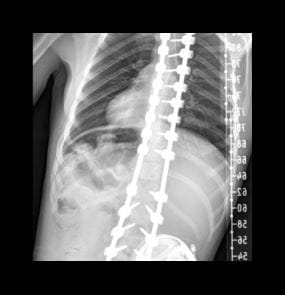

Paige’s spine after surgery with rods and screws inserted using FIREFLY® Technology.

When Dr. Hardesty placed the guides on the patient's spine during surgery, she could see precisely where to place rods and screws – despite the significant twists and turns of her young patient's spine.

“Using FIREFLY® decreases the risk of spinal cord, nerve and tissue damage. Knowing you're in the right place the first time you attempt to place a pedicle screw is safer for the patient’s anatomy. It also reduces the patient’s exposure to radiation and anesthesia, further enhancing patient safety,” Dr. Hardesty says.